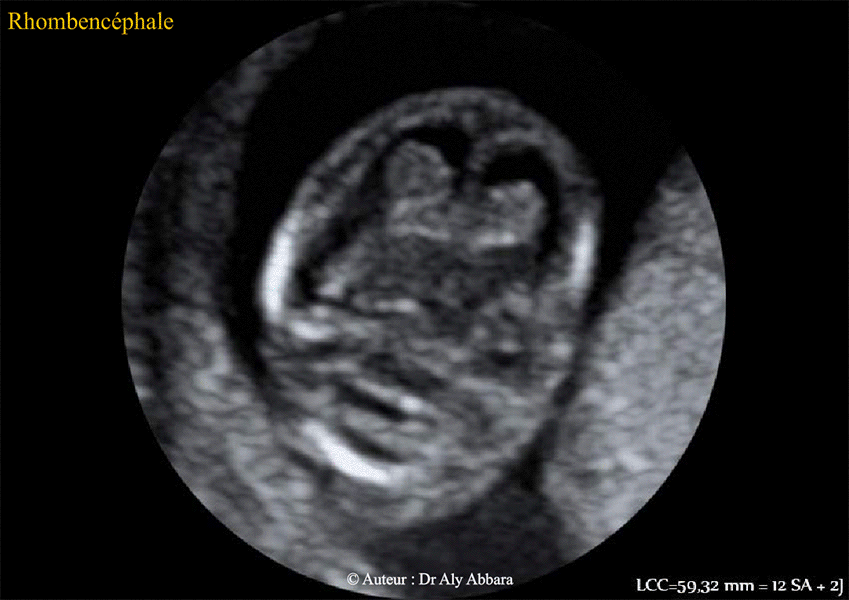

Cerveau fœtal - coupes échographiques axiales (la 2° coupe est légèrement inférieure à la première) - embryons âgé de 12 SA + 2 jours.

Les éléments anatomiques du cerveau issus du rhombencéphale et identifiables à l'échographie sur ces coupes : pont, 4° ventricule (ou clarté intracérébrale à ce terme de grossese), la poche de Blake et le cervelet.